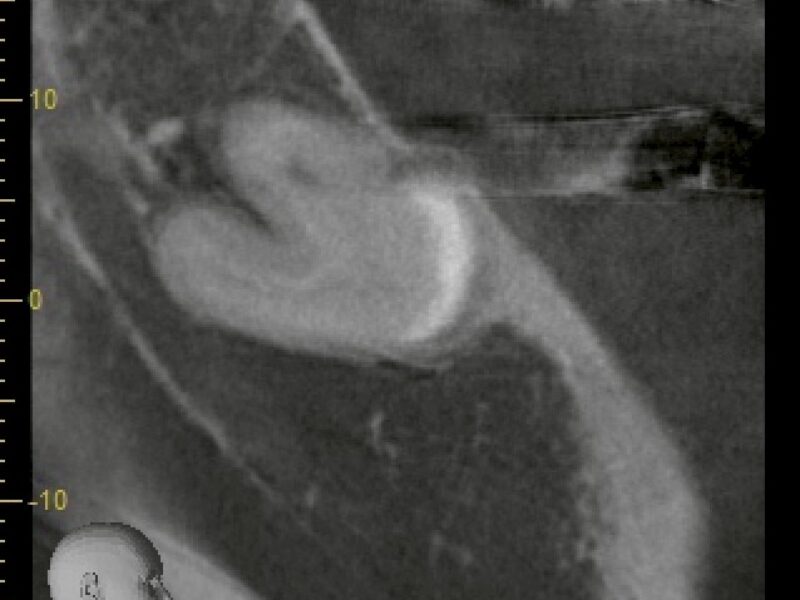

特徴4高精度診断を可能にする「歯科用CT」 -